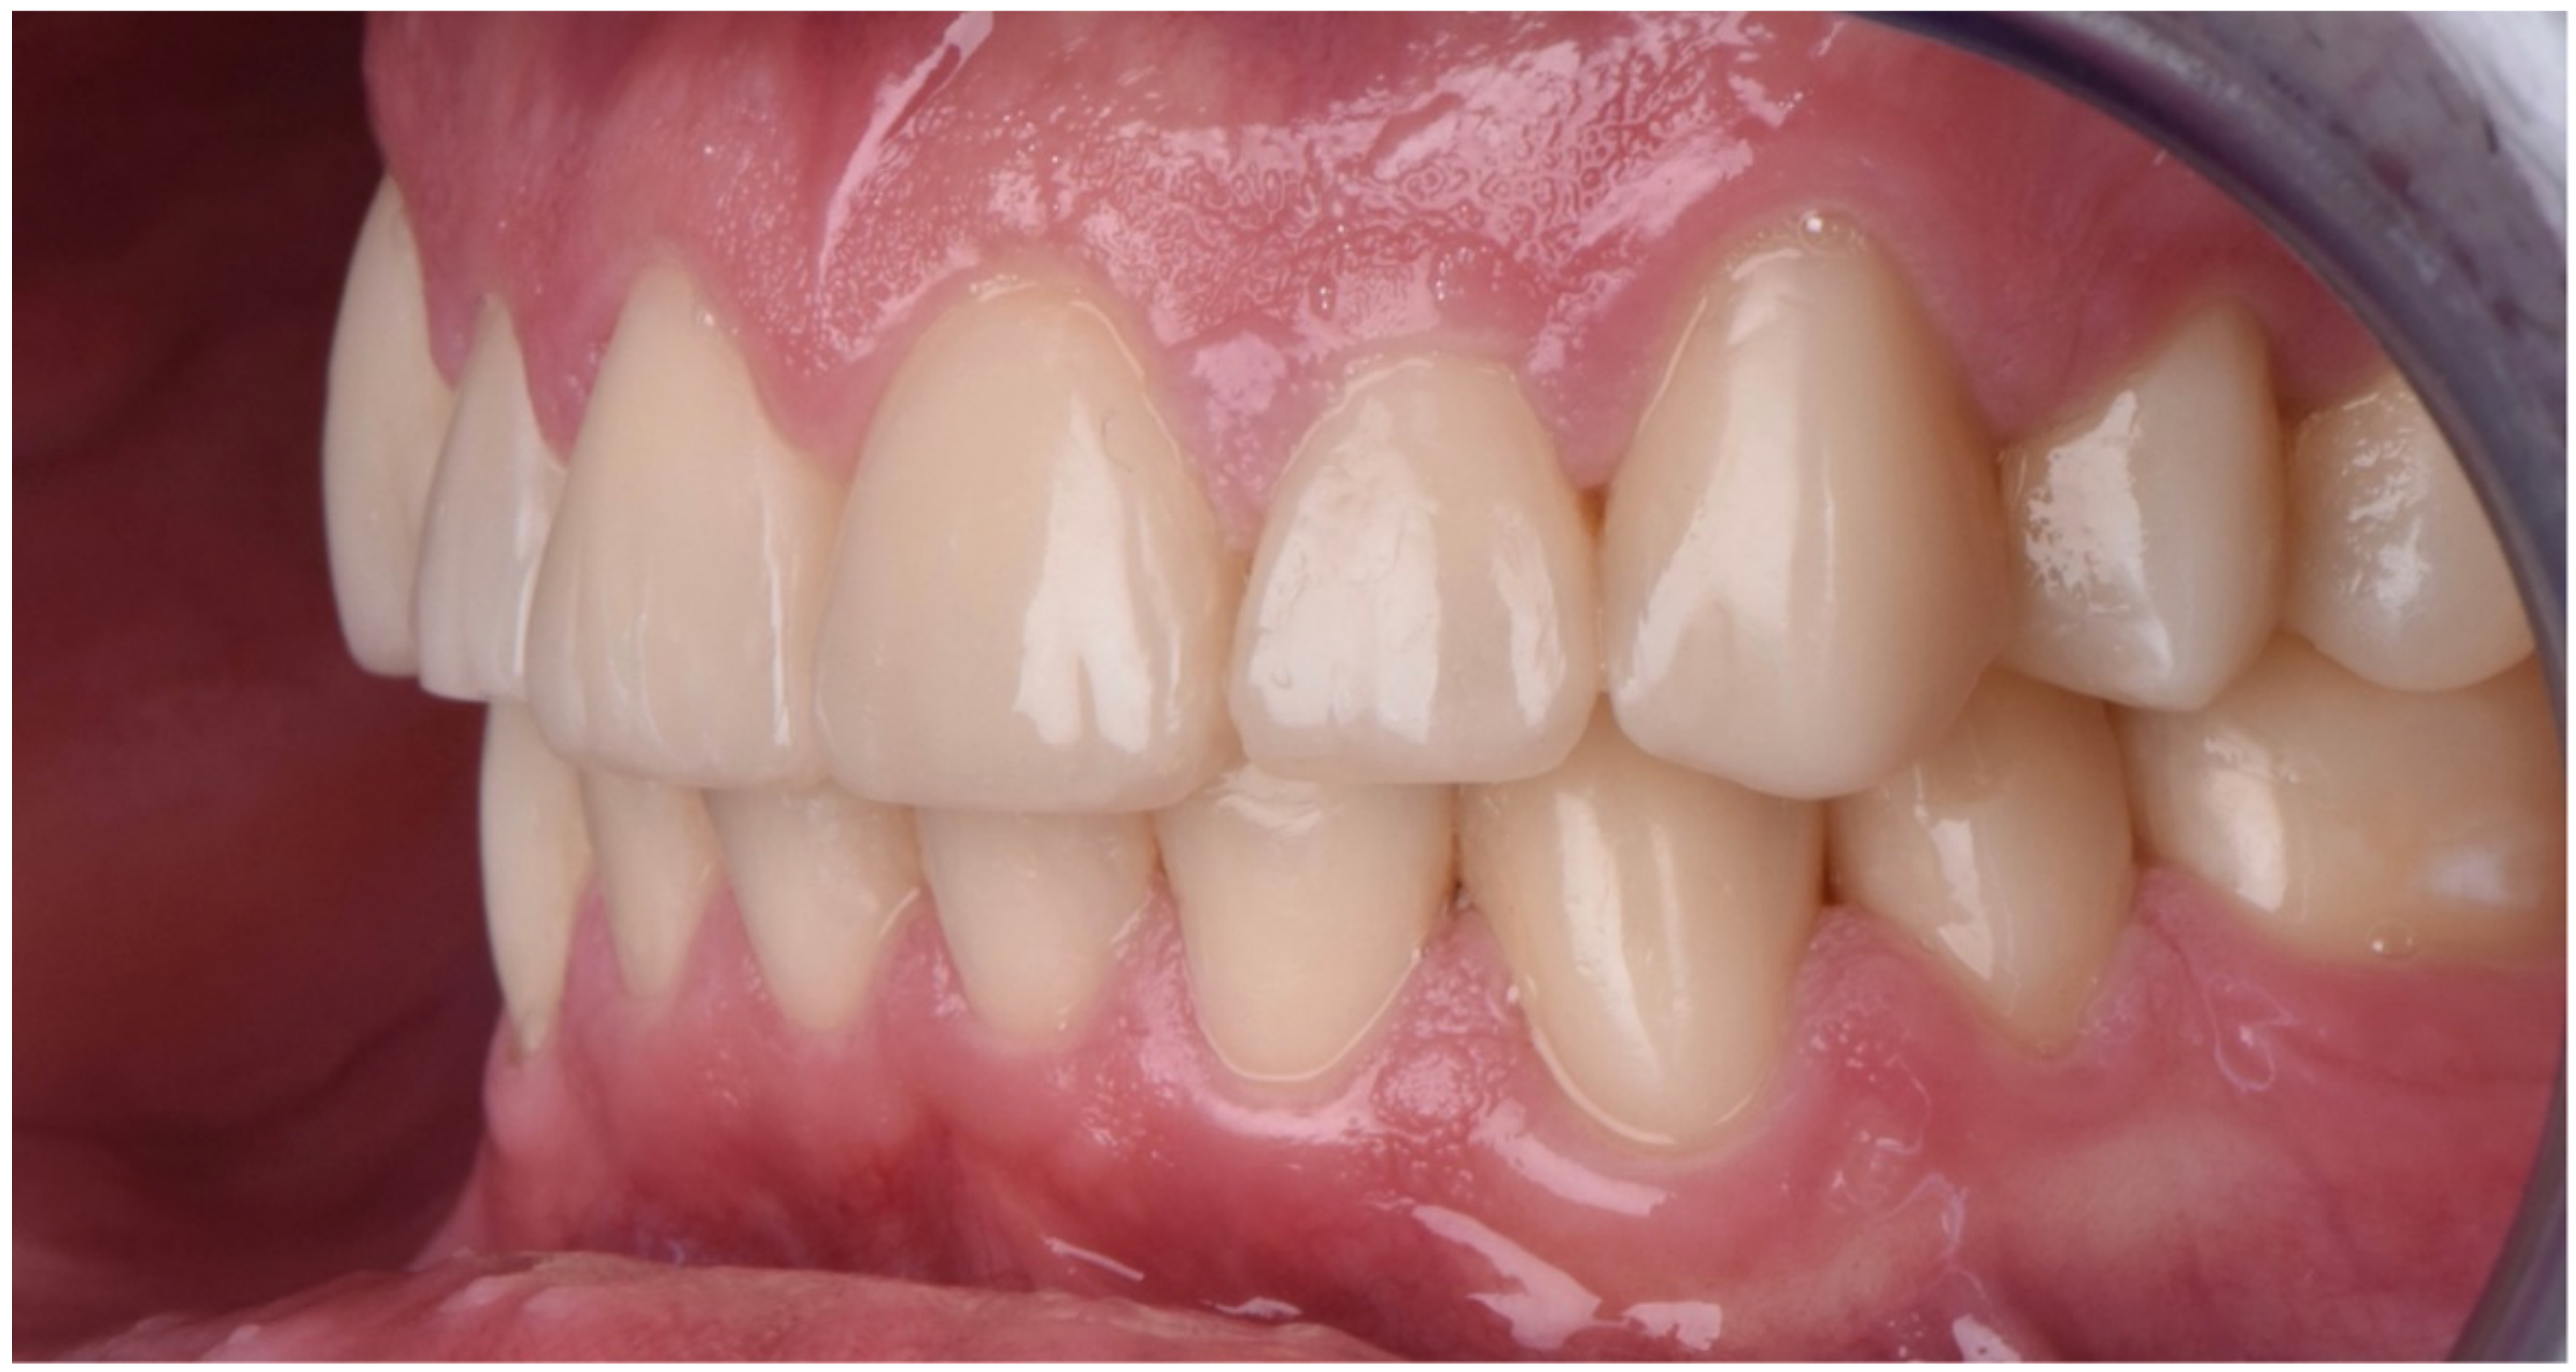

2.2. Restorative Phase